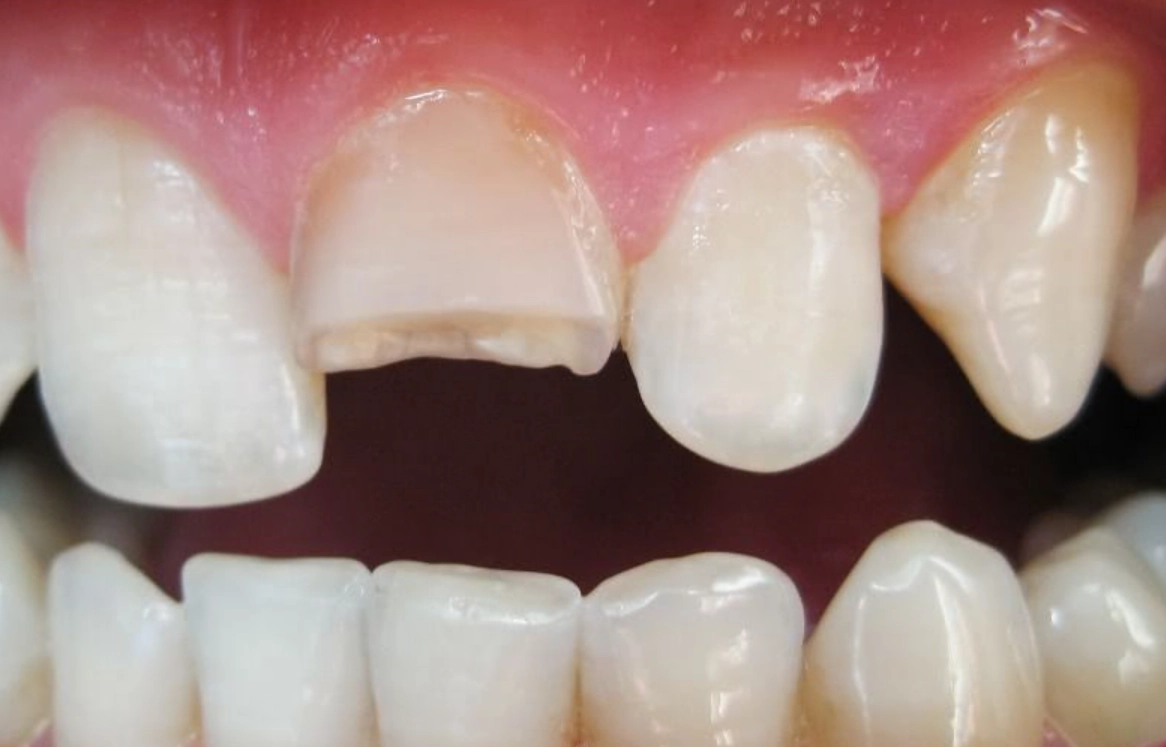

情境一:吃東西時,牙齒突然崩裂一半

這是最常見的版本。夢裡你在享用美食,可能是堅果、肉排或甚至只是麵包,咬下去的瞬間聽到「喀」一聲,然後半顆牙齒就留在食物裡。

這種夢境強烈關聯到「無力感」與「失控」。牙齒是我們主動攻擊、咀嚼、消化外界資訊(食物)的工具。它在執行本該最勝任的工作時突然故障,往往映射現實中,你覺得自己在某個擅長的領域或日常任務上「失手了」、「搞砸了」。可能是工作上一個很有把握的提案被挑戰,或是自認處理得很好的人際關係突然破裂。